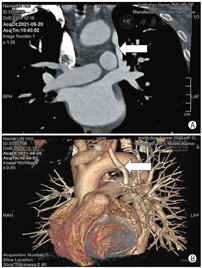

患者男,46岁,主因左上肢无力2个月余,加重1 d入院。既往高血压病史10年,高脂血症病史2个月。头颅MRI:右侧基底节、放射冠及额叶急性梗死灶。颅颈动脉CTA:轻度动脉硬化,以双侧颈总动脉分叉处为著。初步诊断:脑梗死(急性期),高血压1级,很高危,高脂血症。患者曾在外院行经胸超声心动图检查未见异常,为除外卵圆孔未闭右向左分流所致脑卒中,申请行右心声学造影检查。静息下左上肢静脉注入激活生理盐水,右心显影后左心内未见显影,随后行Valsalva动作激发试验,发现注射激活生理盐水后左房先于右房显影,且左房内微泡浓度短暂高于右房(图1)。更换为右上肢静脉注射激活生理盐水,静息下及Valsalva动作后均右心显影,左心未显影。鉴于上述结果,考虑左侧静脉连接异常,行经胸超声心动图检查,重点扫查胸骨上窝切面。在降主动脉左侧可测及异常静脉,宽约8 mm,与左无名静脉相通,汇入右侧上腔静脉,彩色多普勒血流显像示静息时异常静脉血流流入左无名静脉,Valsalva动作后可见异常静脉内血流短暂逆流,结合右心声学造影表现,考虑异常静脉为永存左上腔静脉,直接或通过左肺静脉汇入左房(图2)。患者行左房肺静脉CT证实永存左上腔静脉经左上肺静脉汇入左房(图3)。

永存左上腔静脉(persistent left superior vena cava,PLSVC)是最常见的主干静脉畸形,在正常人群中发病率为0.1%~0.3%[1]。PLSVC始自左无名静脉和左颈总静脉的交界处,90%以上通过扩张的冠状静脉窦引流入右房,少数通过无顶冠状静脉窦引流入左房,直接引流入左房或通过左肺静脉引流至左房比较罕见[2]。PLSVC一般不引起血流动力学改变,但会影响静脉操作如中心静脉置管、起搏器植入以及射频消融等;PLSVC引流入左房可导致左向右以及右向左分流,可能引起发绀、矛盾栓塞、感染性心内膜炎、播散性感染等。血栓和菌栓一般来源于左上肢,临床进行左上肢静脉操作时需注意防止此类并发症发生。

PLSVC连接左肺静脉或左房的患者分流量不大时,心腔大小一般没有明显变化,无需特殊治疗,如出现矛盾栓塞等并发症时,可行经导管封堵或外科矫正[6],目前国内罕见类似病例的报道。结合头颅MRI等影像表现,考虑本例患者此次发病与动脉粥样硬化相关,并未发生矛盾栓塞,患者未行心导管检查或外科手术,诊断未得到进一步证实,存在一定的缺憾。